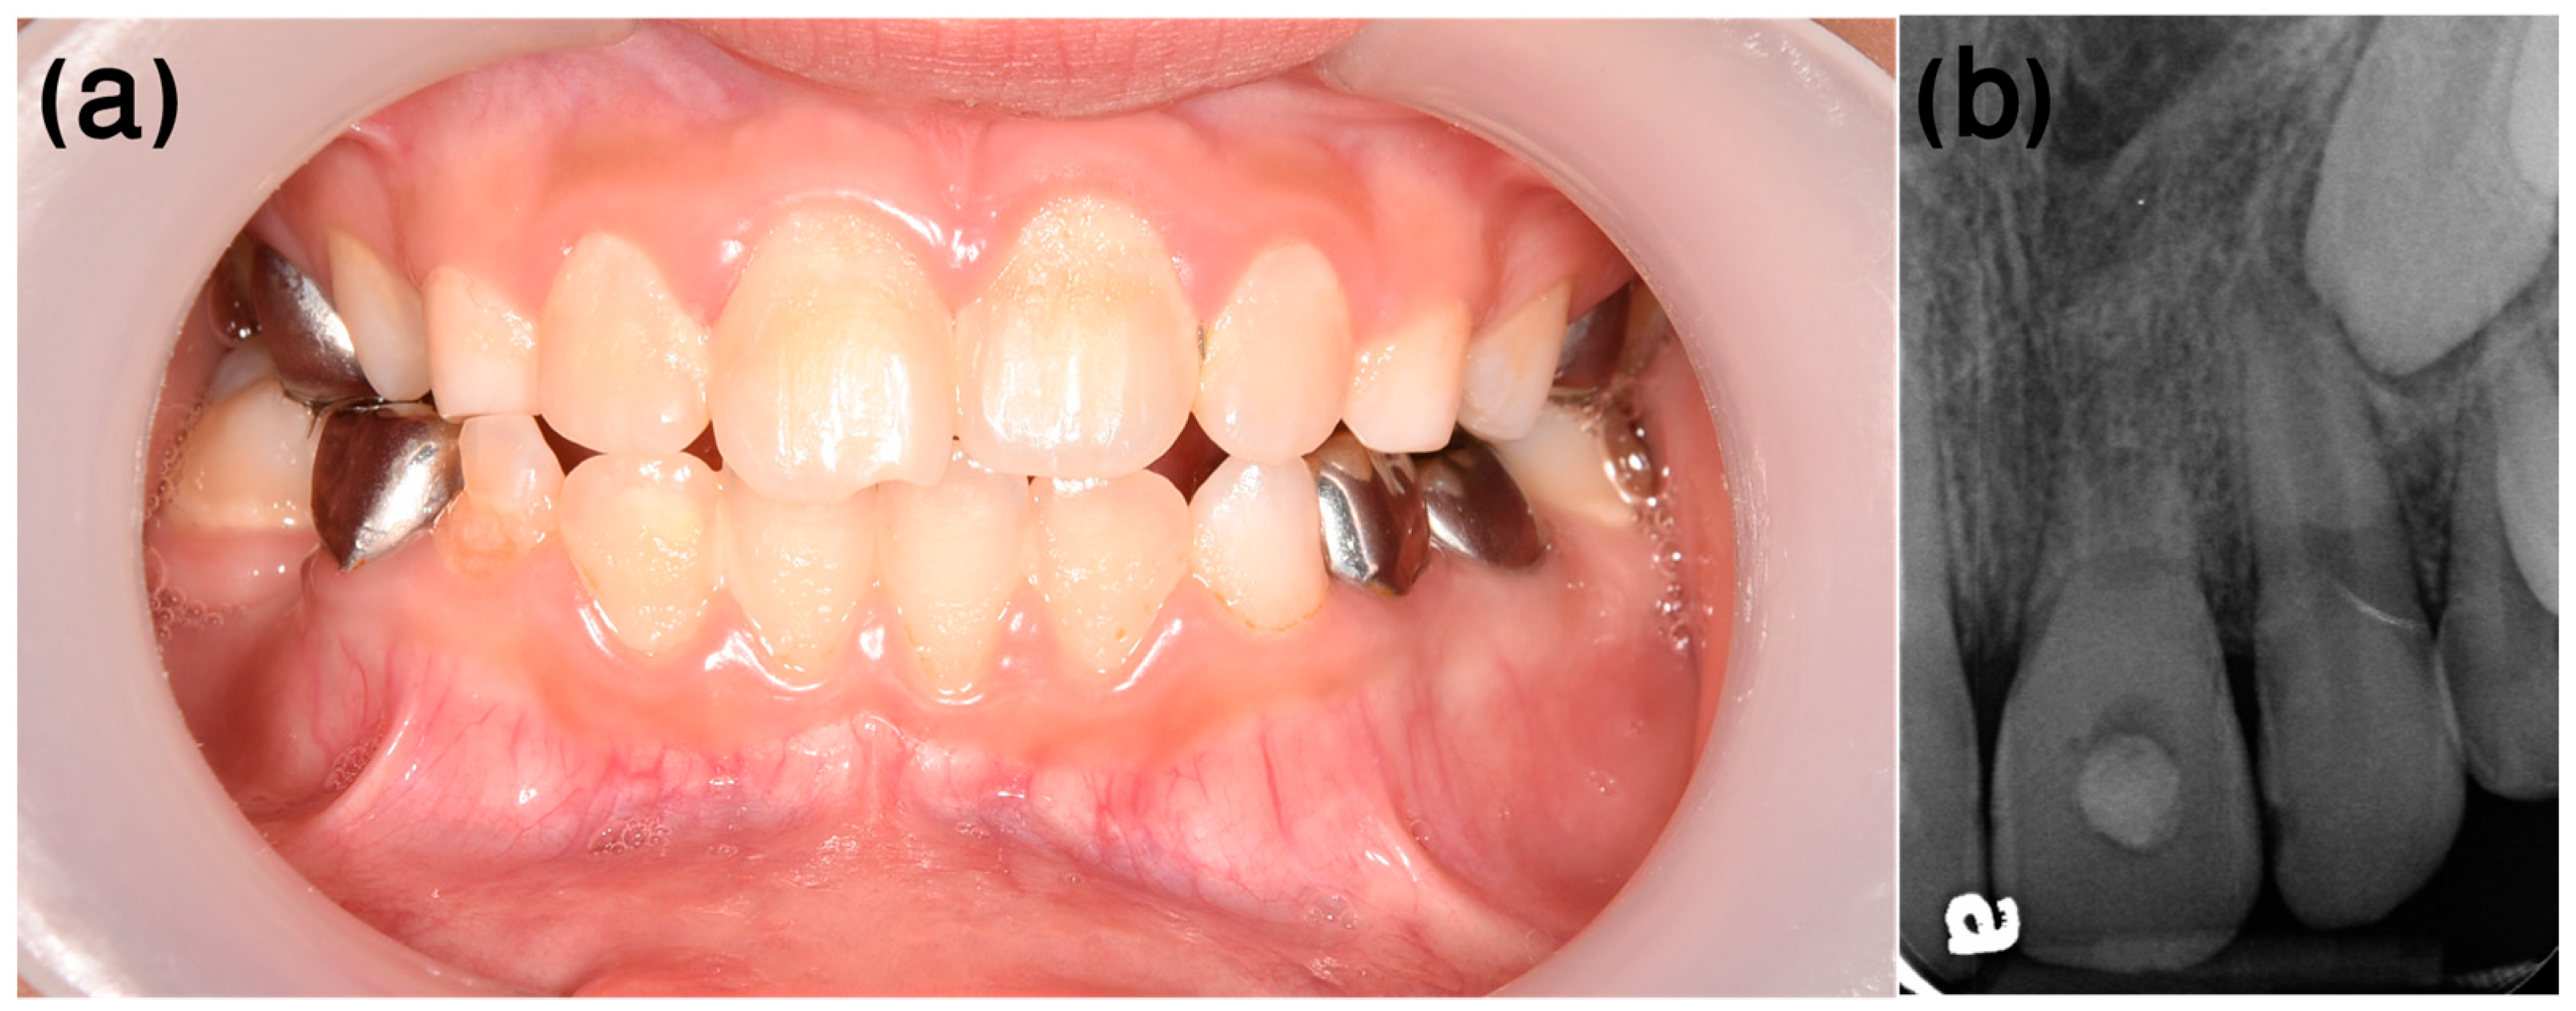

3.1. Case 1

- Dental history

- Clinical procedure

- Follow-up